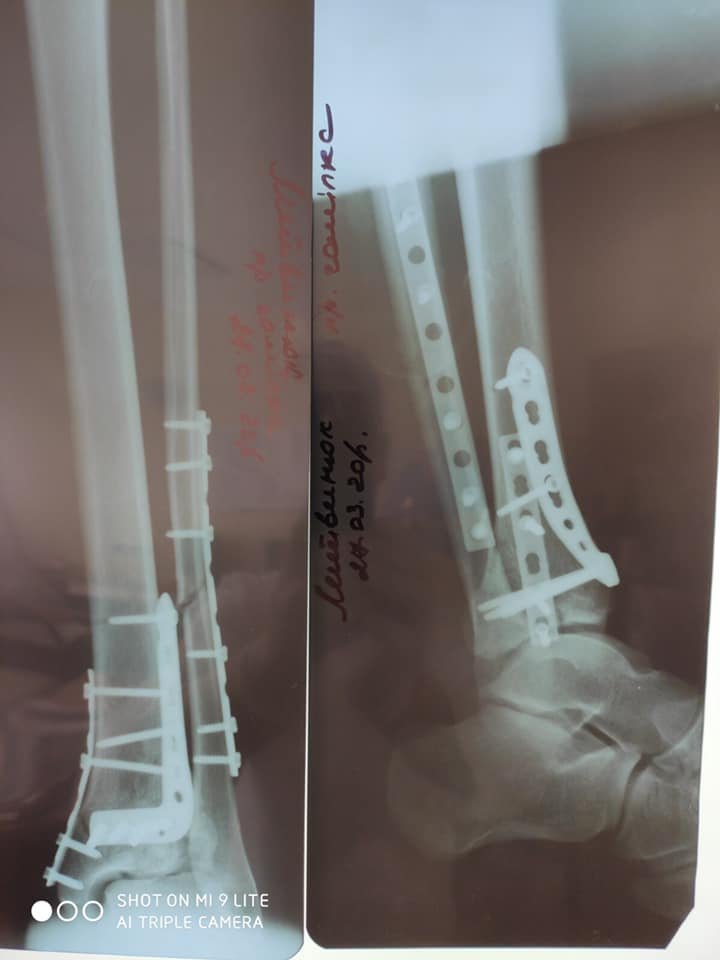

"У відділенні лікувався хворий, який впав з 4-х метрової висоти з переломом обох нижніх кінцівок. Йому успішно зробили оперативне втручання - металоостеосинтез дистальних метаепіфізів правої і лівої нижніх кінцівок з кістковою пластикою", - розповів лікар ортопед-травматолог Леонід Шеремета.

Медики міської лікарні застосовують кращі практики сучасних технологій остеосинтезу, зокрема мінімально-інвазивні методи (Minimally Invasive Plate Osteosynthesis MIPO) фіксації переломів з використанням пластин з кутовою стабільністю.

Перевагою цього методу лікування є збереження функціональної рухомості кінцівки та найближчих суглобів в період зрощення, прискорення консолідації та відновлення опорної функції кінцівки.